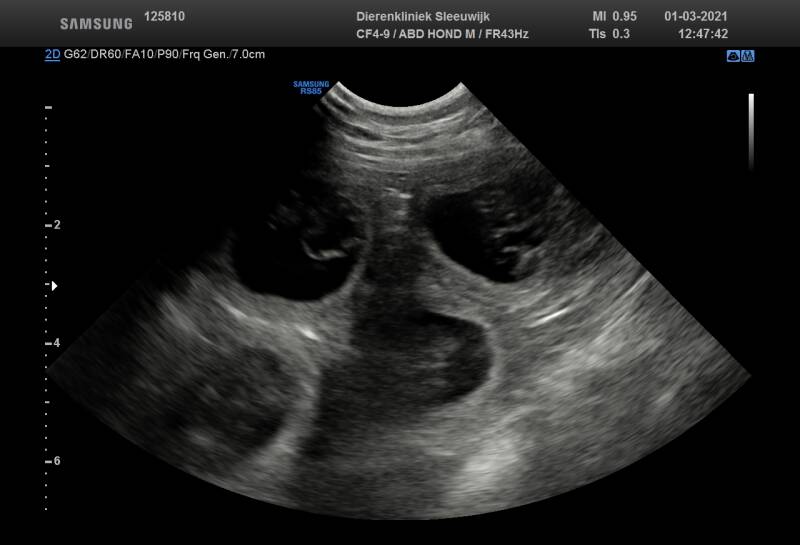

De echo's van 01/03/2021.

Deze echo's zijn gemaakt op 1 maart 2021.

Het moment dat we er achter kwamen dat Noesja 4 weken drachtig is.

Op deze echo foto's waren de puppy's 1,5 cm.